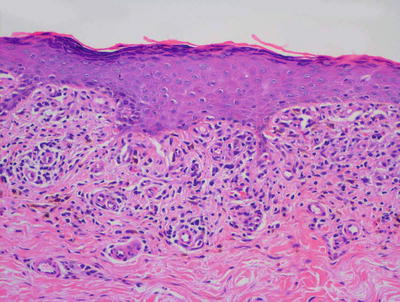

The diagnosis of lichen striatus requires careful clinicopathologic correlation. The epidermis is generally either unremarkable or displays focal spongiosis that some authors have described as occurring within the lower portions of the epidermis [24]. Parakeratosis is present in many cases. Acanthosis may be seen with elongation of the rete ridges [25]. An interface dermatitis is present, although often there is only a focal lymphocytic infiltrate of the basal layer leading to keratinocyte vacuolization and destruction (Figs. 4.5 and 4.6). Earlier lesions tend to have a more confluent and band-like infiltrate along the epidermal junction, and this diminishes in intensity with progressive age of the lesions. The dermis contains a superficial and deep perivascular infiltrate of lymphocytes and histiocytes. A similar infiltrate is seen around hair follicles and especially around eccrine coils [26]. Eosinophils and plasma cells are not part of the reactive process in most cases. While there are histologic features for lichen striatus as described, for the most part these are not specific and can be seen in a variety of lesions.

A papillomatous epidermis with an underlying band-like infiltrate is characteristic of lichen striatus. A dense inflammatory infiltrate is also seen surrounding eccrine ducts

Fig. 4.6

An intense interface dermatitis with abundant exocytosis and focal spongiosis within an acanthotic epidermis is seen in some cases of lichen striatus